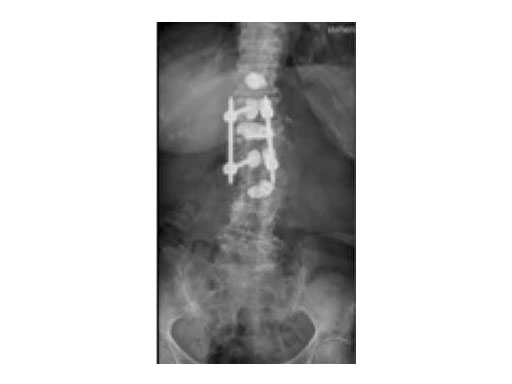

A 78-year-old woman was affected by steroid induced osteoporosis. She had persisting pain (mechanic and muscular) due to static imbalance (hyperkyphosis) and nonunion 8 months after a minor trauma with a vertebral compression fracture and vertebra plana of L1, and development of symptomatic stenosis of the spinal canal with loss of mobility over time. Pre-existing degenerative lumbar scoliosis was increased by the fracture.